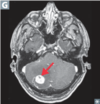

Subdural hematoma

Red: cresecent shapped hemorrhage

Blue: acute on chronic